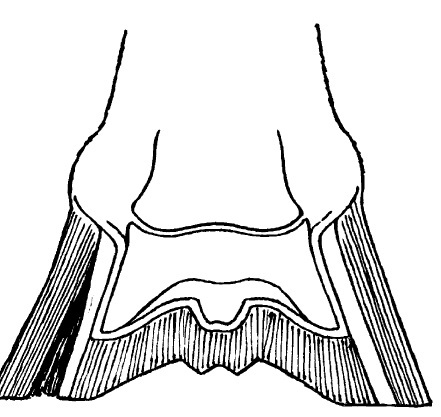

Figure 91-3. Illustration showing hollow wall on the left side (dark area) of a hoof.